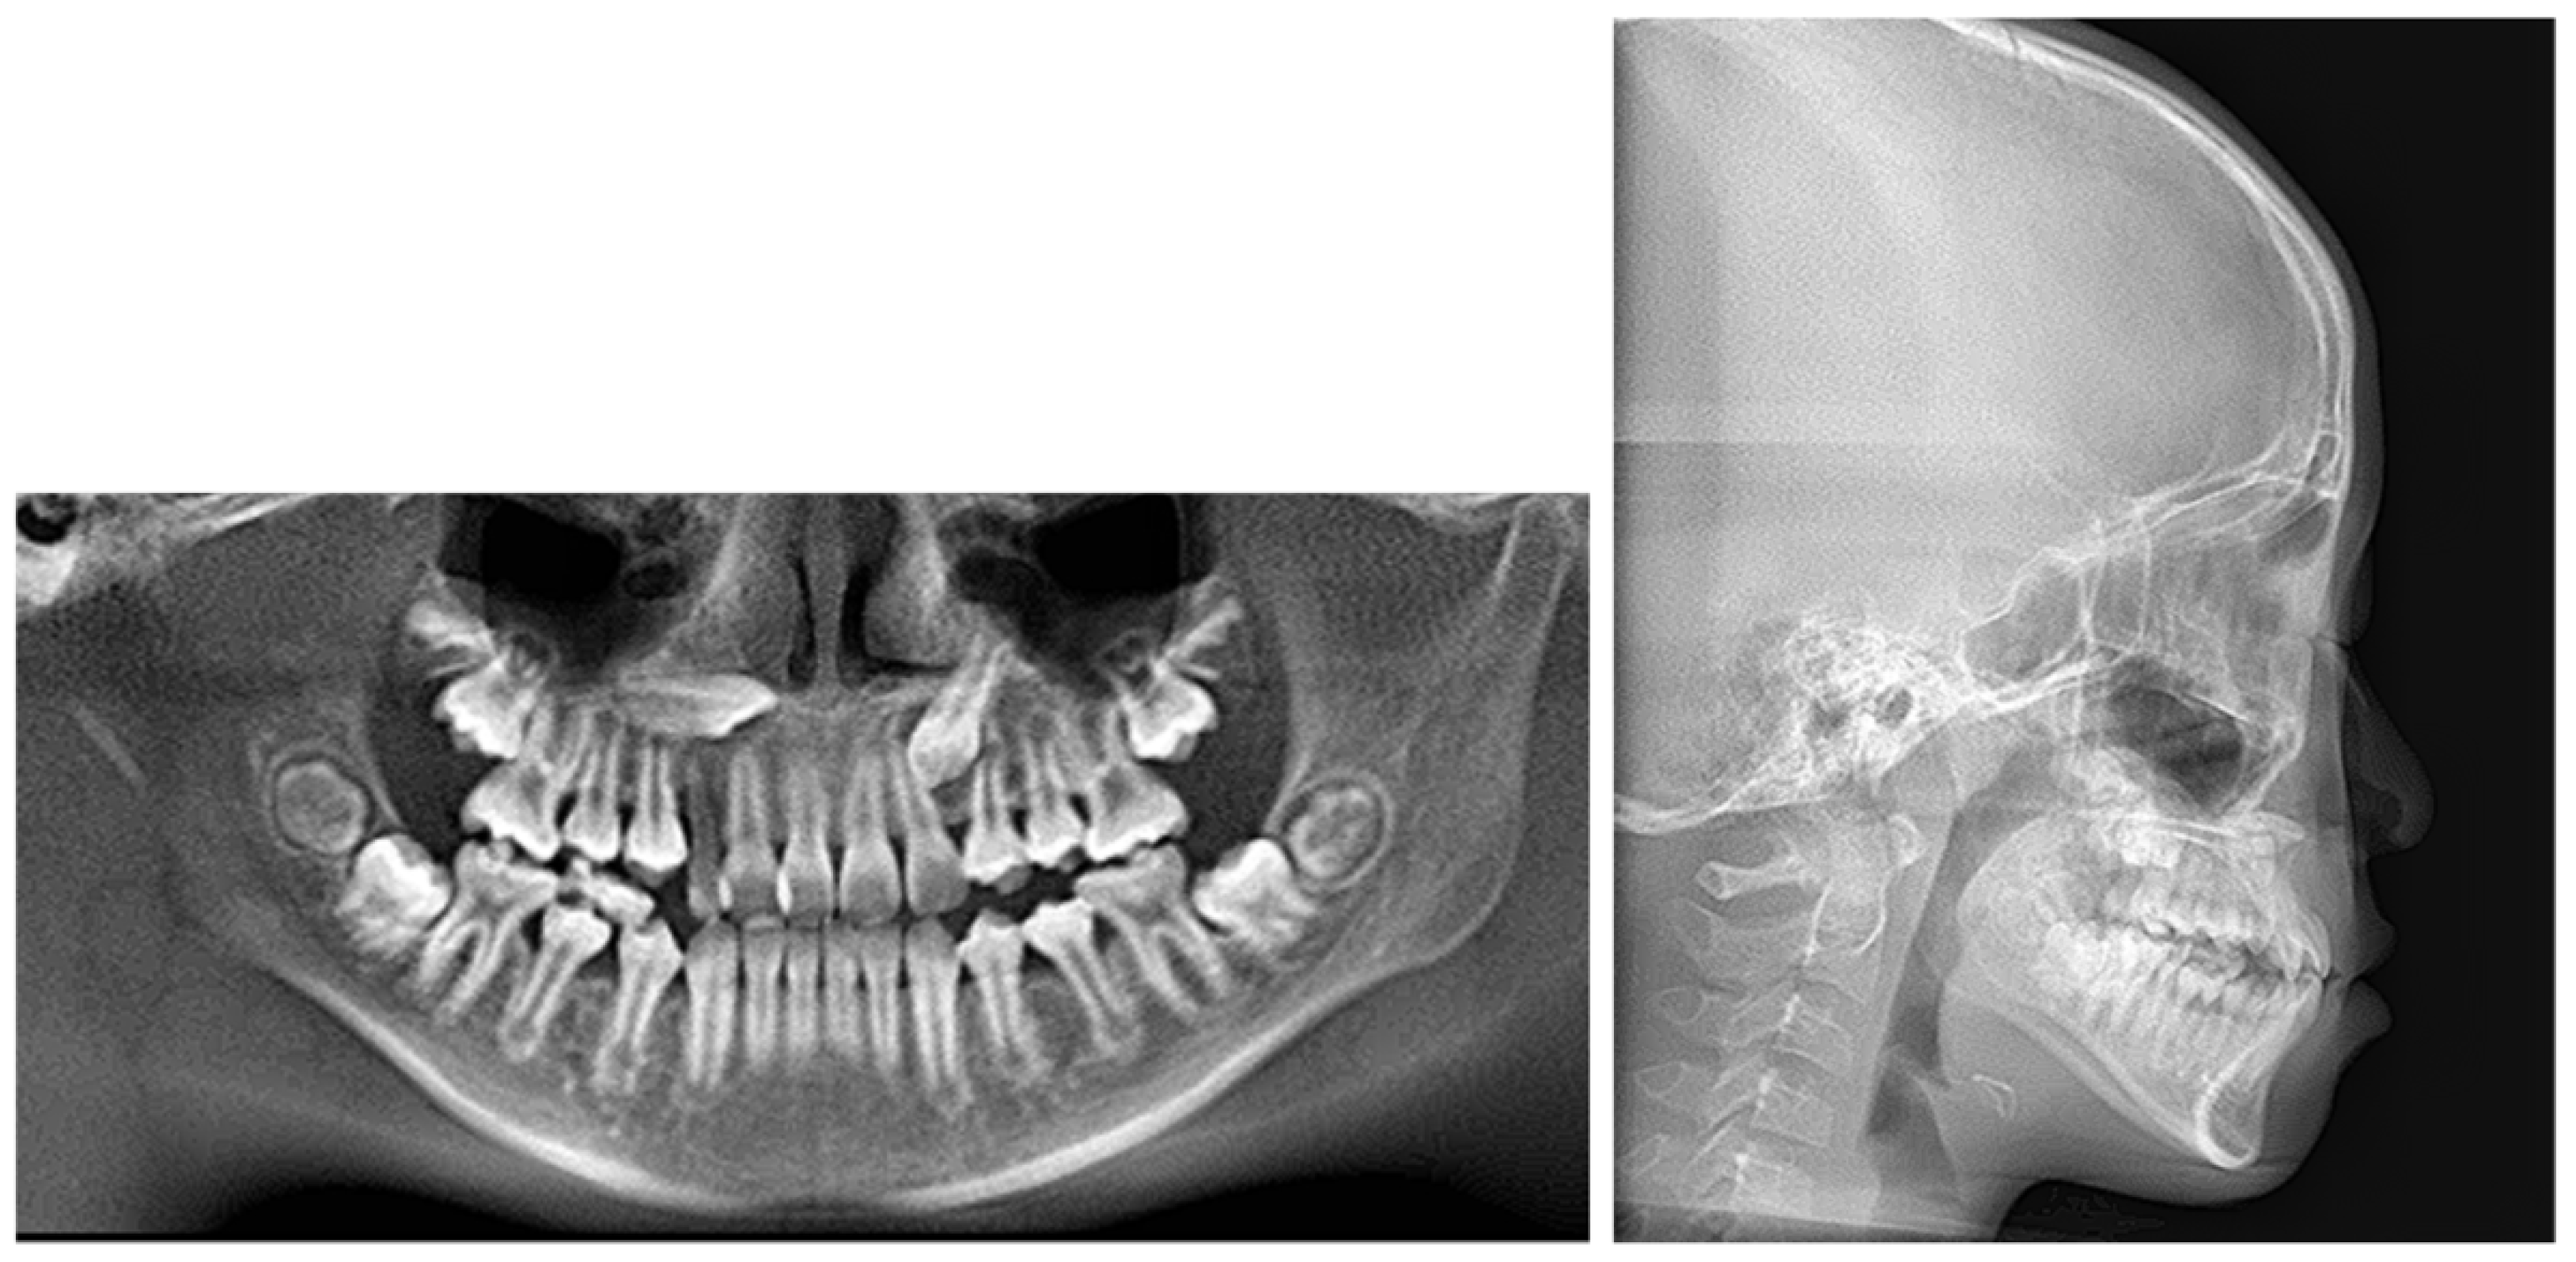

2. Case Presentation

2.1. Diagnosis and Etiology